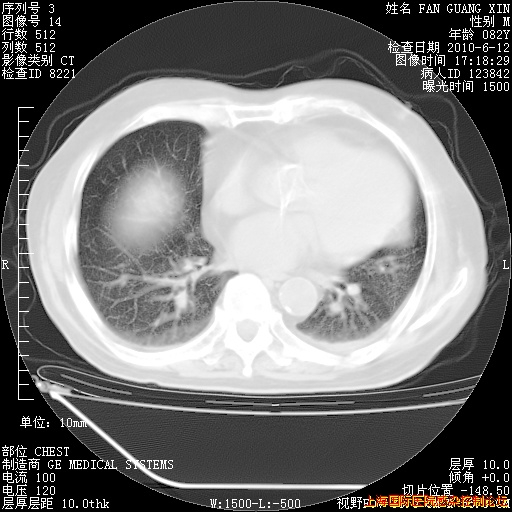

今天复查CT

今天CT

整整相隔30天的肺部CT好像有所好转啊。甲强龙减量第3天,需要观察体温。